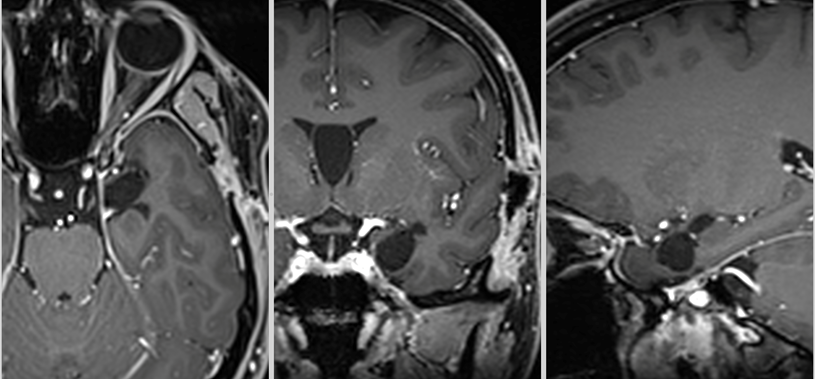

Pentru pacienți, aceste episoade sunt adesea greu de înțeles și pot fi însoțite de teamă și incertitudine. Investigațiile imagistice au adus însă explicația: RMN-ul cerebral a evidențiat o mică tumoră profundă, situată pe fața internă a lobului temporal stâng, la nivelul hipocampului și al nucleului amigdalian.

Deși tumora era relativ mică – aproximativ doi centimetri – localizarea ei era extrem de delicată. Hipocampul este una dintre structurile centrale ale creierului, implicată în memorie și procesarea emoțiilor, iar lobul temporal stâng joacă un rol important în limbaj.